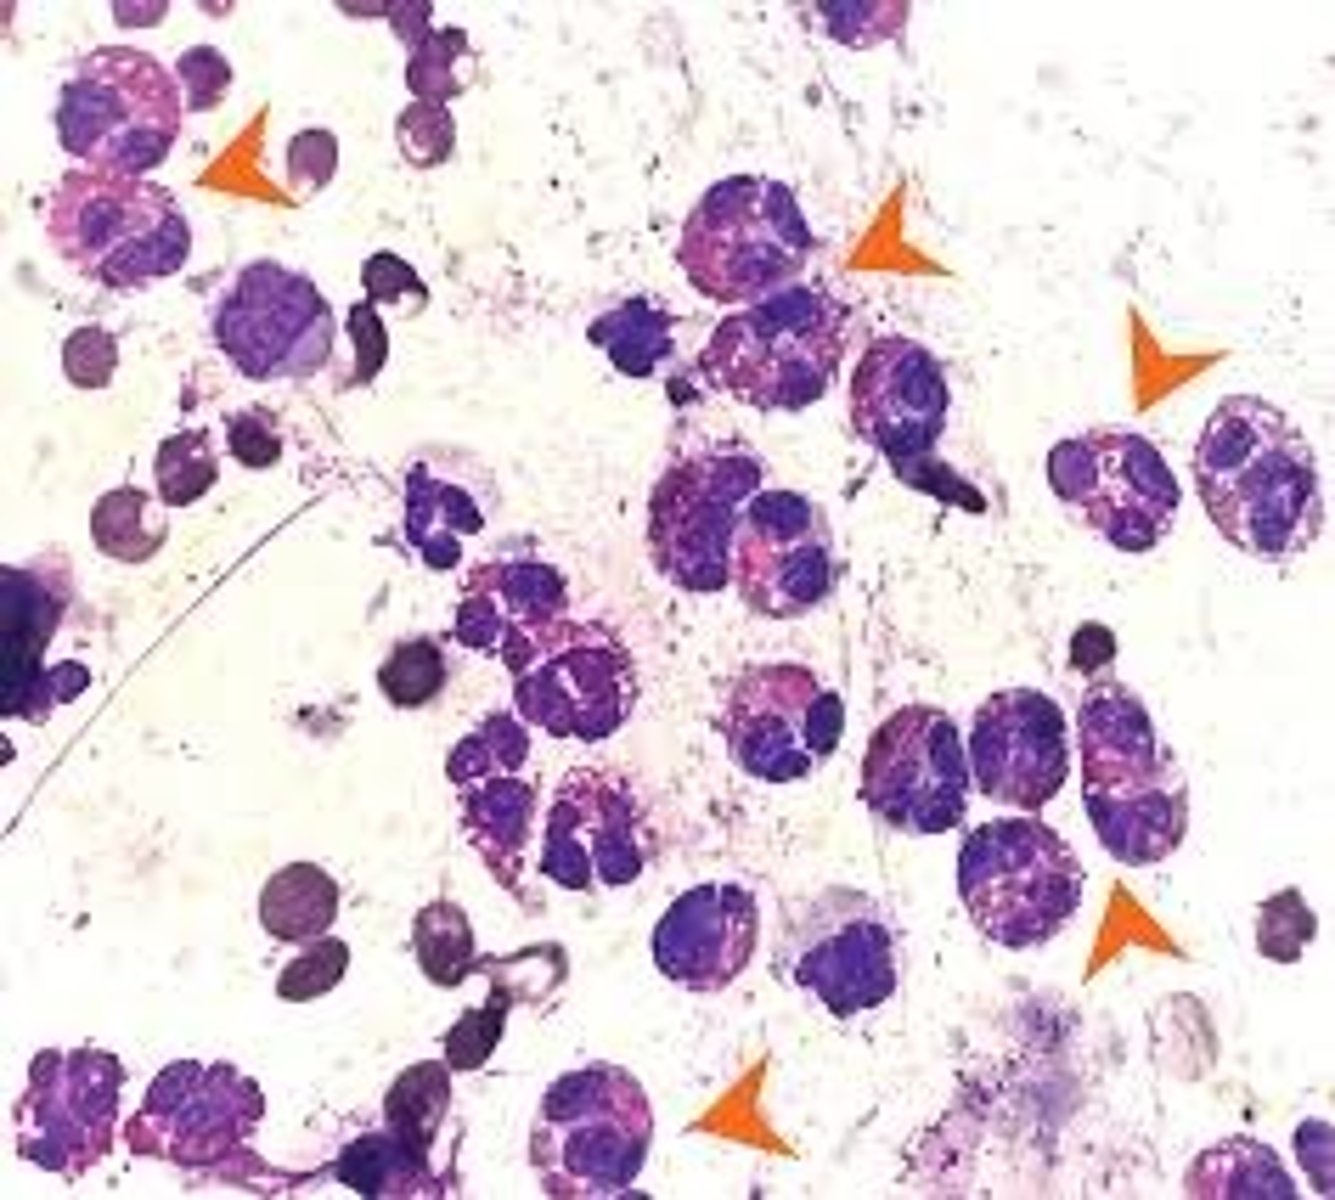

What is it? Sample collected from a mass

Mast cells